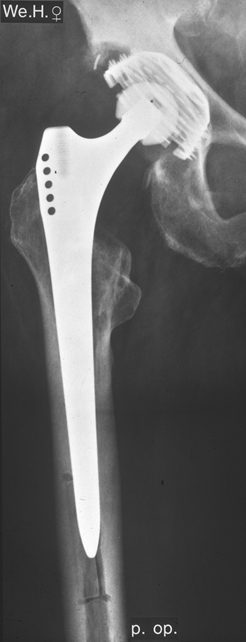

Fallbeispiel

Weiblich, 55 Jahre. Es zeigt sich eine schwere Dysplasiearthrose der

rechten Hüfte (links im Bild) sowie eine Subluxation des linken Hüftkopfes mit

partiellem Kopfeinbruch.

Beide

Hüftgelenke wurden in einer Operation ersetzt. Das Röntgen zeigt das

Ergebnis 10 Jahre postoperativ. Beide Hüften sind stabil im Knochen

verankert, die Patientin ist außerordentlich zufrieden.